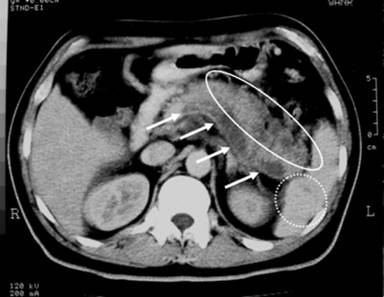

The most commonly affected part of the pancreas was the body region (100%; Figure 1), followed by the head (75%; Figure 2) and tail (50%; Figure 3). The involvement was typically multi-focal (75%; Figures 1 and 2) and in the form of micro-abscesses. Only one patient (25%) had a large focal solitary abscess (Figure 1), affecting the body of the pancreas. Other associated pancreatic findings included splenic vein thrombosis (Figure 2), peripancreatic inflammations and peri-pancreatic fat streaking. Extra-pancreatic manifestations included blood (4 patients), liver abscesses (3 patients; multiple micro-abscesses (Figures 3 and 4) or large ‘honeycomb’-like abscesses), ascites (2 patients; Figures 3 and 4), splenic abscesses (2 patients; Figures 2 and 4) (which also has the ‘honeycomb’ appearance), psoas abscesses (2 patients) and lung (1 patient).

Figure 2. Axial computed tomography image showing multiple abscesses (hypoechoic lesions) in the body and tail regions of the pancreas (oval), splenic vein thrombosis (long tubular hypoechoic structure) indicated by white arrows and splenic micro-abscesses (dotted circle). Follow-up scan showed resolution of the abscesses and recanalization of the splenic vein (Case #2). |